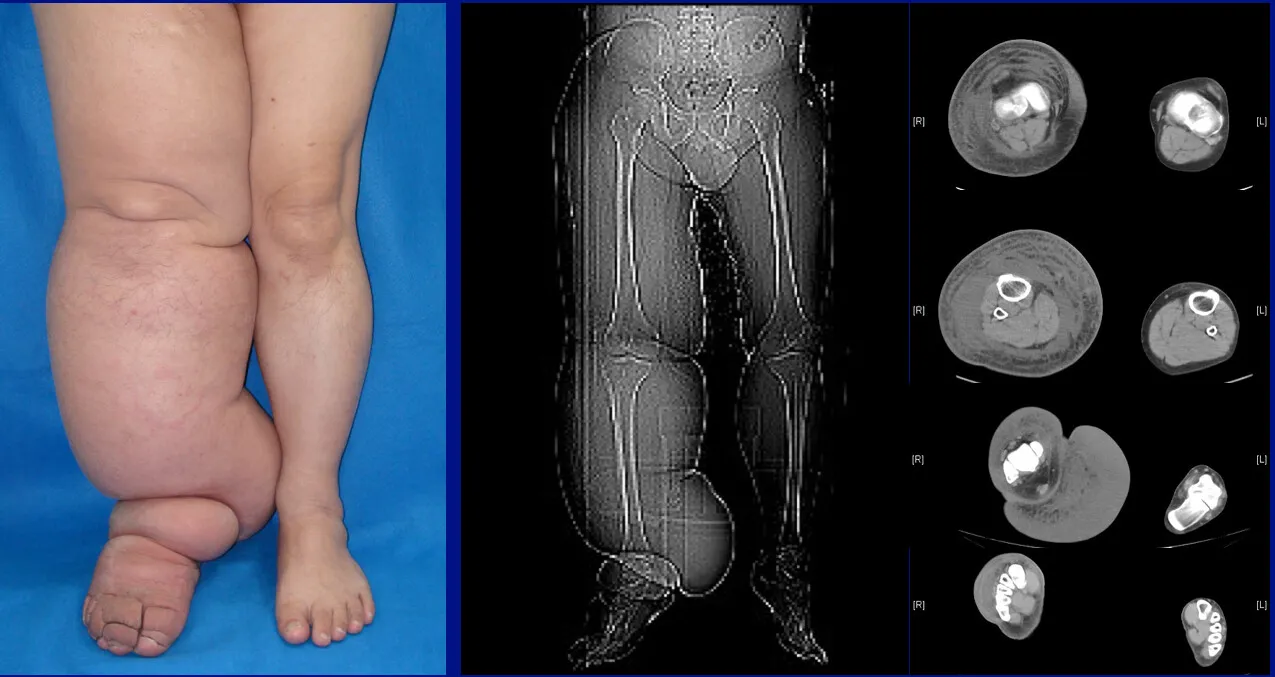

Milroy hastalığının başlıca belirtisi, vücutta meydana gelen şişlik (ödem) ve lenfatik sıvı birikimidir. Ancak hastalık her bireyde aynı şekilde kendini göstermeyebilir. Genellikle bacaklar, ayaklar, kollarda ve bazen de karın bölgesinde şişlikler oluşur. Milroy hastalığının diğer belirtileri şunlar olabilir:

- Bacaklarda, Ayaklarda ve Kollarda Şişlik: Lenf sıvısının birikmesi sonucunda, genellikle bacaklar, ayaklar ve kollarda şişlikler ortaya çıkar. Şişlik başlangıçta hafif olabilir ancak zamanla büyüyebilir.

- Ciltte Sertleşme ve Kalınlaşma: Şişlikler uzun süre devam ettiğinde, cilt üzerinde sertleşme ve kalınlaşma görülebilir.

- Ultrason ve Diğer Görüntüleme Yöntemleri: Bacaklardaki ve kollardaki şişliklerin iç yapısının incelenmesi için ultrason gibi görüntüleme teknikleri kullanılabilir.